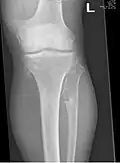

A noticeable lump in relation to an extremity may be the first presenting symptom. Multiple deformities can arise, namely coronal plane deformities around the knees, ankles, shoulders, elbows, and wrists. For example, genu valgum (knock knees), ankle valgus, ulnar bowing and shortening, and radial head subluxation are encountered. The majority of affected individuals have clinically manifest osteochondromas around the knee. Forearm involvement in HMO is considerable.[1][7] Intra-articular osteochondromas of the hip can induce limitation of range of motion, joint pain and acetabular dysplasia.[2] Likewise joint pain at other locations and neurovascular compression can occur. Furthermore, functional disability in regard to activities of daily living can be a presenting feature. Spinal deformity pain or neurological compromise should arouse suspicion of involvement of the vertebrae.[3][8] Furthermore, short stature may occur and is generally disproportionate. Such manifestations usually result from disruption of physeal growth especially that osteochondromas typically arise at the metaphyseal ends of long bones in close proximity to the physis.[1][7]

The diagnosis of HMO is based upon establishing an accurate correlation between the above-mentioned clinical features and the characteristic radiographic features. Family history can provide an important clue to the diagnosis. This is supplemented by testing for the two genes in which pathogenic variants are known to cause HMO namely EXT1 and EXT2. A combination of sequence analysis and deletion analysis of the entire coding regions of both EXT1 and EXT2 detects pathogenic variants in 70–95% of affected individuals.[3][7] The hallmark of radiographic diagnosis is the presence of osteochondromas at the metaphyseal ends of long bones in which the cortex and medulla of the osteochondroma represent a continuous extension of the host bone. This is readily demonstrable in radiographs of the knees.[3][1]